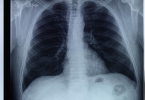

肋软骨与胸骨连接处无菌性炎症常由搬运重物、剧烈咳嗽等引发。疼痛在深呼吸、咳嗽或按压胸壁时加剧,局部无红肿但压痛明显。X线检查多无异常,需与心绞痛鉴别。治疗可采用双氯芬酸钠缓释片、塞来昔布胶囊等抗炎药,配合局部理疗。